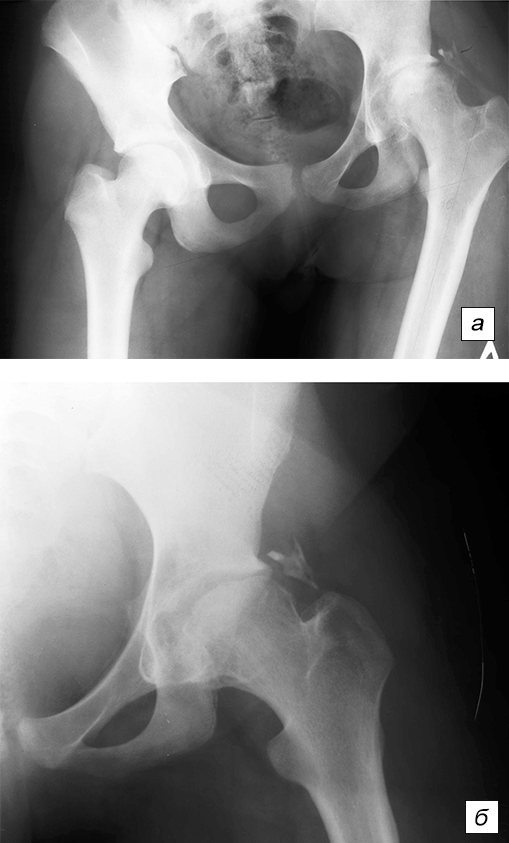

Здоровье суставов: Трохантерит и его влияние на мышцы